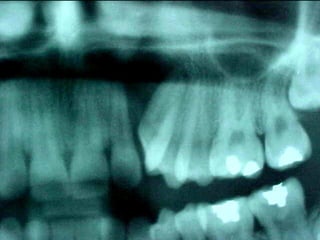

En el estudio radiográfico determinamos que el factor causal fué un foco séptico

dentario a nivel de segundo molar inferior izquierdo.